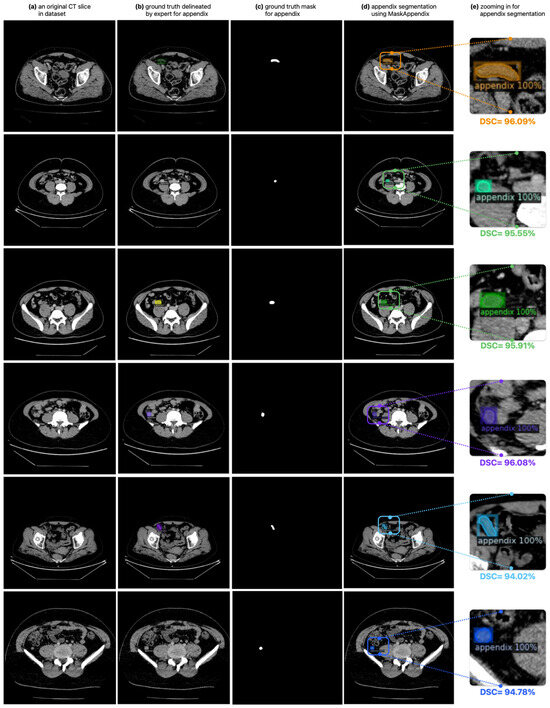

3.1. Results